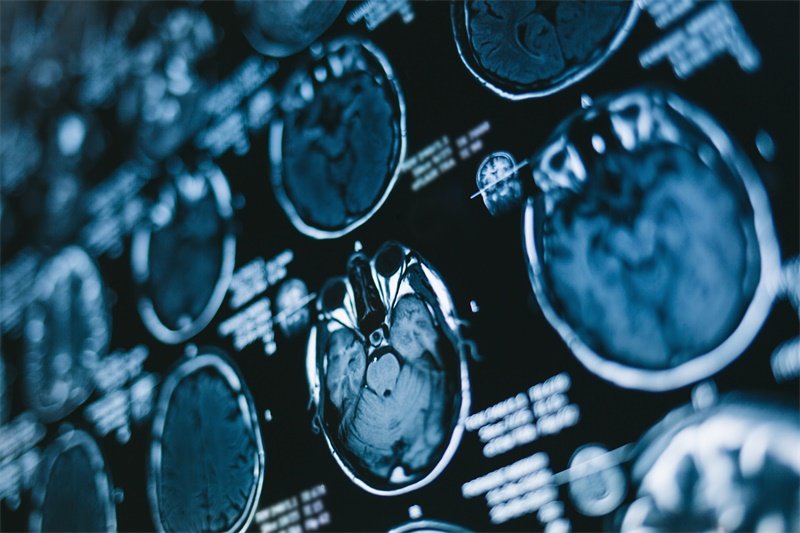

1. 影像学检查

影像学检查是诊断的主要手段,尤其是磁共振成像(MRI)和计算机断层扫描(CT)。MRI能够提供详细的软组织结构图像,使医生可以准确看到占位的大小、位置和相关组织的情况。